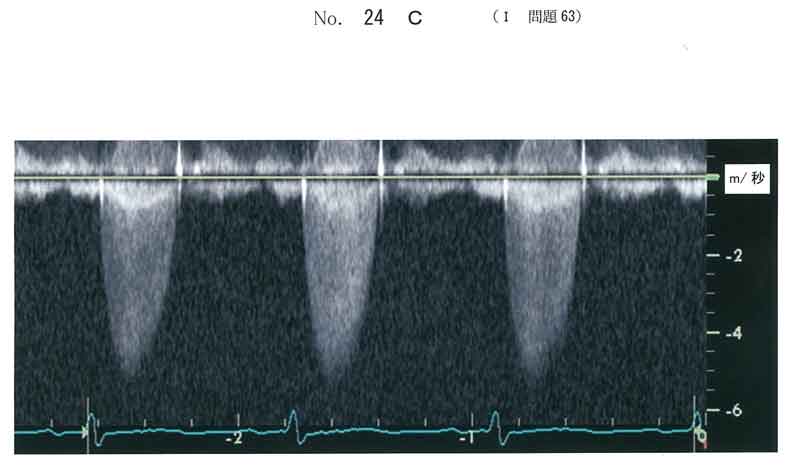

c。(AS)

最高血流速度が4m/秒をこえており、高度の大動脈弁狭窄症。

有症状の高度AS→弁置換術